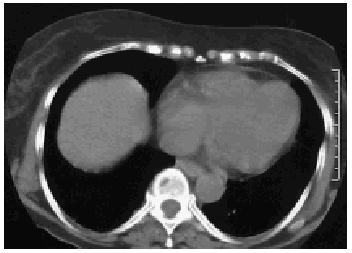

Mujer de 79 años de edad en quien, durante la realización de una TC abdominal con contraste, se produjo de forma accidental la administración de 100 ml de aire a través de una vena periférica con un flujo de 2 ml/s, motivo por el que realizó una TC torácica, donde se observó una burbuja aérea en el ventrículo derecho (fig. 1). La paciente en todo momento se encontró asintomática.

Figura 1.